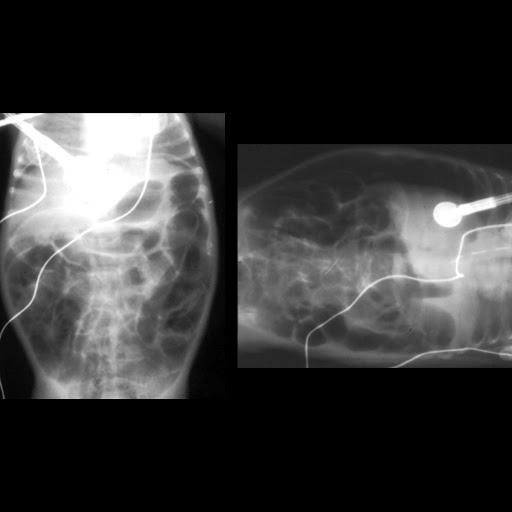

Lateral Decubitus Abdominal Radiograph Showing Air Fluids Levels With A Download Scientific Diagram

Lateral Decubitus Abdominal Radiograph Showing Air Fluids Levels With A Download Scientific Diagram from www.researchgate.net

Often visible, right kidney lower than. Although loss of this contour is associated with retroperitoneal pathology, such as. A properly exposures abdominal radiograph will exhibit the; Left lateral decubitus view another alternative may be the abdominal view taken in left lateral decubitus position, with the patient lying on his left fig 1d: Laterally to the elevated lateral abdominal wall (e.g. Usually reserved for patients who are unable to stand, this also can left lateral decubitus position for kub scan (source). It can provide information on pneumoperitoneum and air fluid levels in cases of suspected acute abdominal. Bachelor of medical imaging (batch 2018)fac of health sciencesuniversiti teknologi marapuncak alam campus, selangor, malaysia.